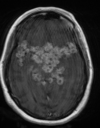

Quais os estágios da neurocisticercose (NCC) ?

Vesicular Vesicular coloidal Nodular granular Nodular calcificado

Qual o padrão da fase nodular granular na NCC?

Qual o padrão da fase vesicular da NCC?

Cisto de paredes finas seguindo sinal do liquor na transição da substância branca com a cinzenta. Nódulo excêntrico que representa o scolex viável. Sem alterações inflamatórias

Qual o padrão a fase nodular calcificada na NCC?

Lesão completamente calcificada sem inflamação Melhor evidenciadas na TC ou RM T2 \*